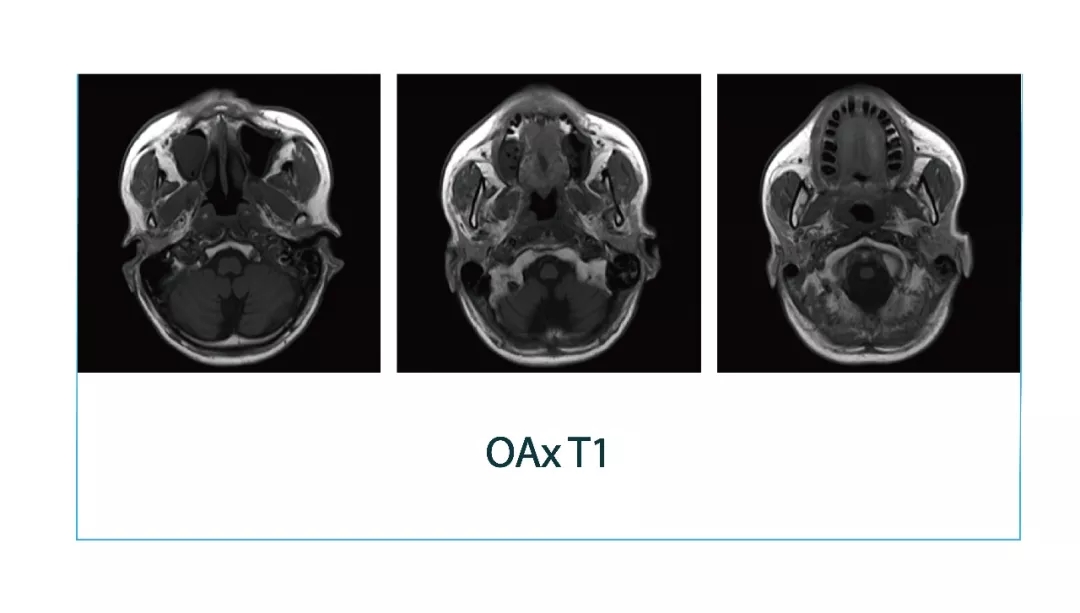

【朗润影像档案】20180323磁共振影像病例结果讨论